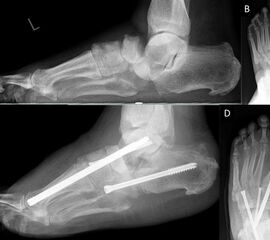

Als Folge der diabetesbedingten Neuropathie kann es zu dem sogenannten Charcotfuß kommen. Bei dieser Komplikation der Diabeteserkrankung kommt es häufig zu einer Zerstörung der Fußwurzelgelenke und -knochen. Dabei springen die Knochen aus den Gelenken (Luxation) und brechen (Fraktur). Der Fuß verliert an Halt und das Fußgewölbe kann zur Fußsohle durchbrechen (Plattfuß). Hierbei treten Druckstellen durch überstehende Knochenfragmente an der Fußsohle auf, die dann zu Hautschäden führen. Sollten hier konservative Therapiemaßnahmen (Polsterung/Schuhzurichtung) versagen, ist eine operative Korrektur angezeigt. Dabei werden die Knochen mittels Platten und langen Schrauben stabilisiert.

Zum Lesen der Bildbeschreibung und Vollansicht bitte Bild anklicken. Fotos: Alexander Mehlhorn

Eine weiterer typischer Verlauf eines Charcot Fußes betrifft die Zerstörung der Bänder und des oberen Sprunggelenks. Der Fuß knickt dabei nach innen, manchmal auch nach außen weg. In Schuhen kommt es meist zu Druckstellen im Bereich des Knöchels. Teilweise ist das Sprunggelenk ist so instabil, dass Laufen nicht mehr möglich ist. Oft sind hier die Möglichkeiten einer konservativen Therapie mit Polsterung/Schuhversorgung nicht mehr ausreichend. Kann der Fuß von außen nicht mehr ausreichend stabilisiert werden, ist eine operative Stabilisierung der abgekippten Gelenke mit Platten und Schrauben notwendig um wieder einen belastbaren Fuß zu erreichen.